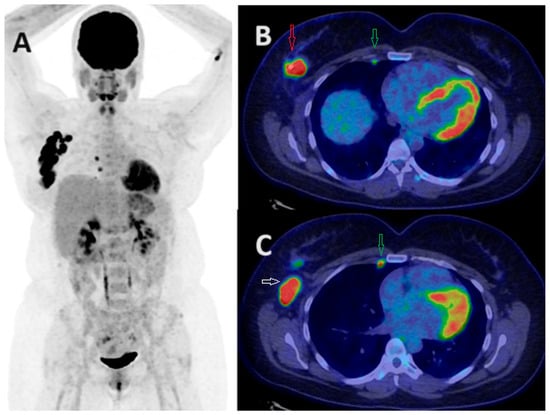

- Kömek, H.; Can, C.; Güzel, Y.; Oruç, Z.; Gündoğan, C.; Yildirim, Ö.A.; Kaplan, I.; Erdur, E.; Yıldırım, M.S.; Çakabay, B. 68Ga-FAPI-04 PET/CT, a new step in breast cancer imaging: A comparative pilot study with the 18F-FDG PET/CT. Ann. Nucl. Med. 2021, 35, 744–752. [Google Scholar] [CrossRef] [PubMed]

- Elboga, U.; Sahin, E.; Kus, T.; Cayirli, Y.B.; Aktas, G.; Uzun, E.; Cinkir, H.Y.; Teker, F.; Sever, O.N.; Aytekin, A.; et al. Superiority of 68Ga-FAPI PET/CT scan in detecting additional lesions compared to 18FDG PET/CT scan in breast cancer. Ann. Nucl. Med. 2021, 35, 1321–1331. [Google Scholar] [CrossRef] [PubMed]